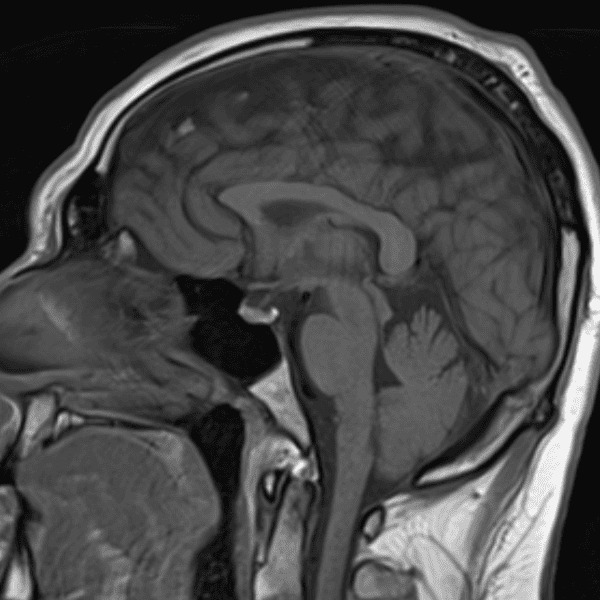

Classic Cases